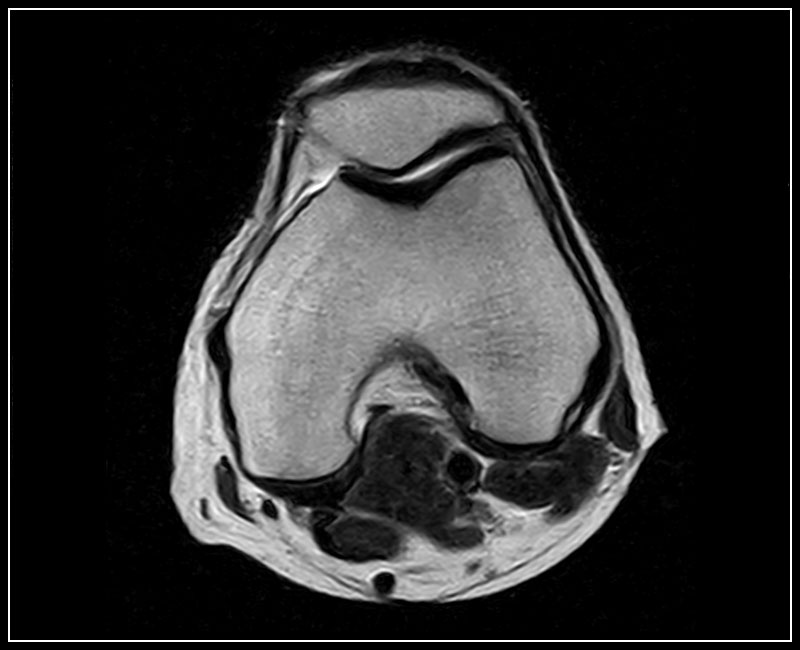

Klinické snímky